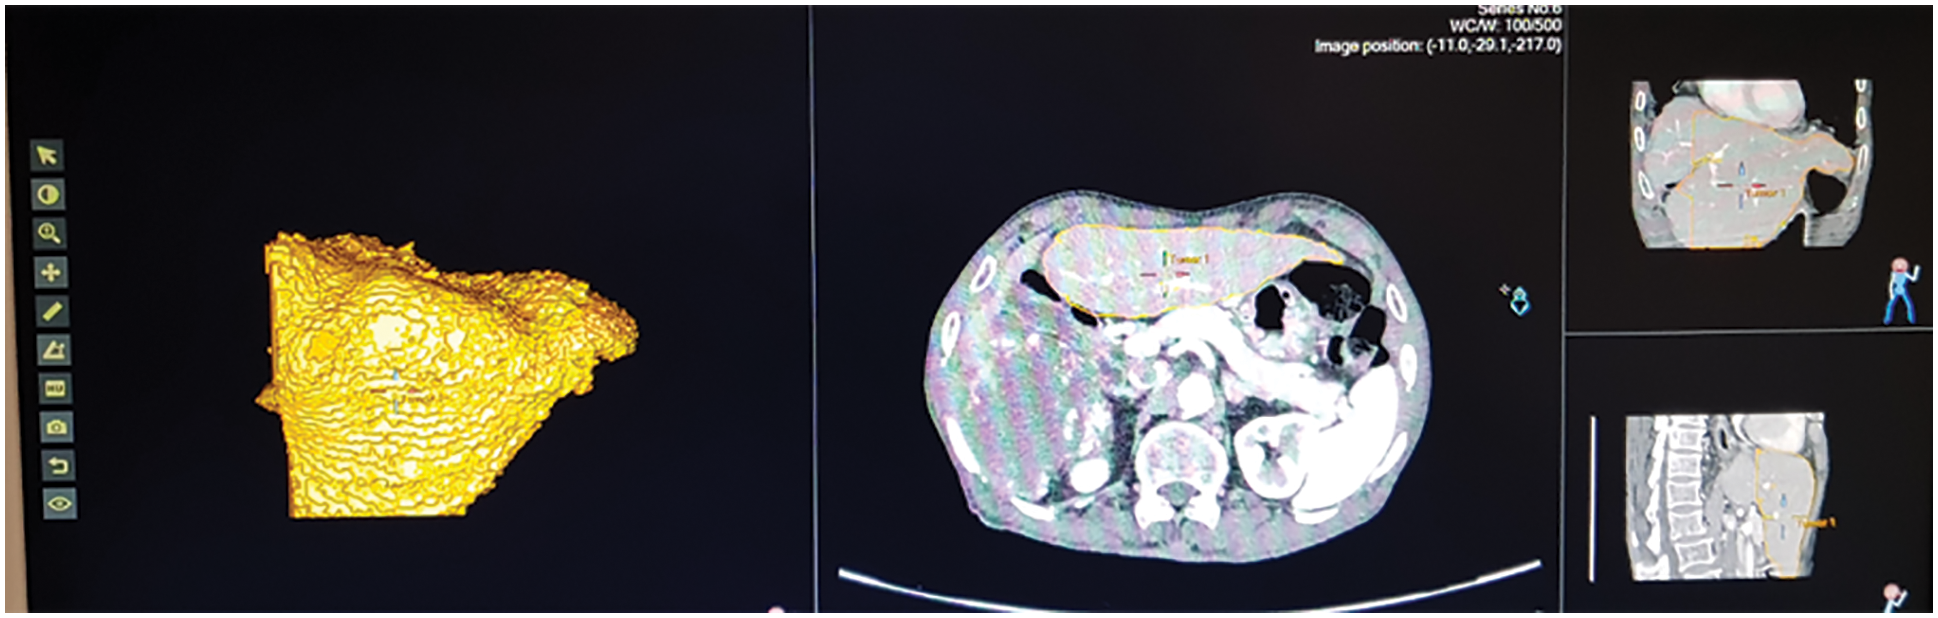

The fatty liver performance is analyzed through ultrasound image and Q values from fatty liver sensor. The tunable Q wavelet transform signal parameters is correlated with ultrasound values. Fig. 12 shows the ultrasound value of severe fatty liver patient. The total liver volume is 2442.13 cc, right liver volume is 554 cc and left liver volume is 1888 cc. The severe fatty liver signal obtained from female patient at the age 61.

Figure 12: Ultrasound of severe fatty liver patient

Fig. 13 shows the ultrasound value of medium fatty liver patient. The total liver volume is 1467 cc, right liver volume is 445.9 cc and left liver volume is 1021.88 cc. The medium fatty liver signal obtained from male patient age 70. Fig. 14 shows the ultrasound of mild fatty liver patient. The total liver volume is 961.86 cc, right liver volume is 365.93 cc and left liver volume is 595.33 cc. The mild fatty liver male patient at age 70. The signals from fatty liver are obtained from fatty liver sensor for sever mild and moderate fatty liver patients. The statistical parameters of the fatty liver signal from TQWT and the ultrasound lab values are correlated using gaussian regression modelling.